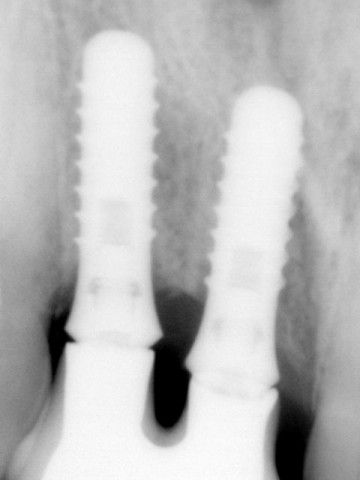

Το περιστατικό στις φωτογραφίες είναι του 1998 και αφορά αποκατάσταση απώλειας δοντιών και οστού στην πρόσθια άνω περιοχή από τροχαίο ατύχημα: